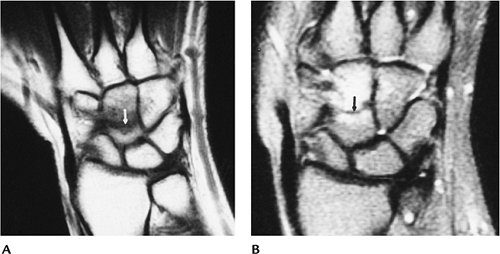

Fractures/Dislocations: Other Carpal Fractures

-

Other carpal fractures occur less frequently than scaphoid fractures.

The triquetrum is the second most common carpal bone fractured followed by the capitate and lunate.

Mechanism of injury: fall on the outstretched hand; compressive or shearing forces.

Treatment: closed reduction and cast immobilization.

Imaging usually can be accomplished with

radiographs. The lateral view is most useful for triquetral fractures.

Subtle injuries may require CT or MRI. -

Complications: nonunion, arthrosis, carpal tunnel syndrome.

![]() |

FIGURE 9-18 Coronal T1-weighted (A) and T2-weighted (B) images of a capitate fracture (arrow) with surrounding edema. Radiographs were normal.